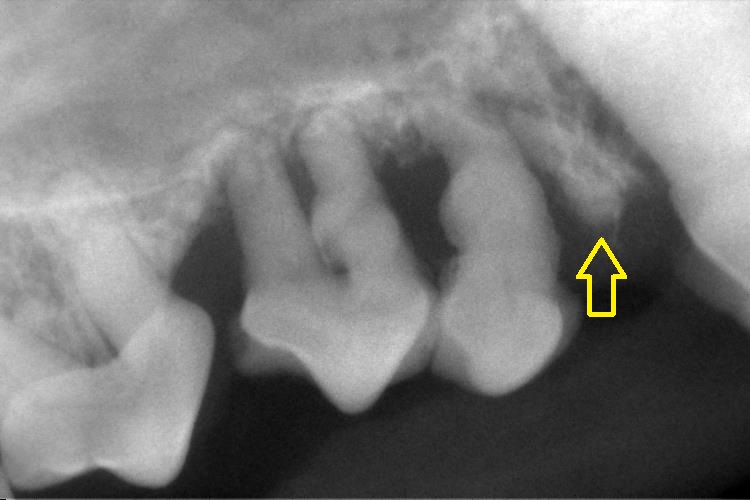

上顎の犬歯は左右ともに歯周ポケットが12mm以上でした。(写真左)

他にも歯周ポケットが深い歯が多く、根分岐部病変(写真右)も見られました。

またポケットが12mm以上あった両側の上顎犬歯に通水テストを行ったところ

口腔鼻腔瘻(こうくうびくうろう)になっていました。(写真右)